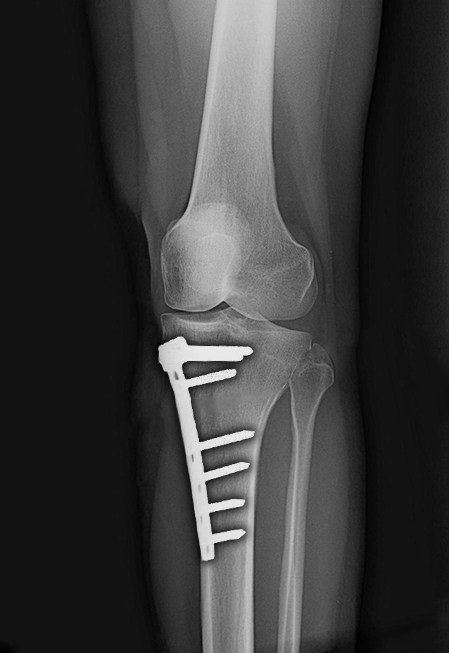

▲ 以鋼板固定

最後別人介紹至□□醫院就醫,沒想到醫生看診不到1分鐘的時間就說要幫她安排最新的「高位脛骨截骨手術」,如此可使內側軟骨承重比例降低,能延後需要接受全人工關節置換手術的時間,以林女士的狀況來說,大概可以多撐個8年再來換人工關節。

本來已經排定要開刀了,但是因為術後必需打6個禮拜的石膏,再加上3個月的復健期,面對手術後可能的副作用與漫長的復健期,林女士怕自己這段時間沒了收入,甚至可能因此丟了工作,所以林女士只好把手術取消了。